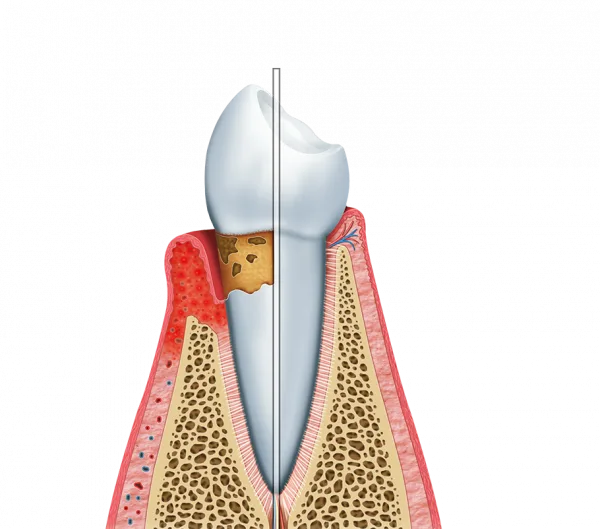

O tratamento de bolsa periodontal é crucial para manter a saúde bucal.

Ele atua diretamente na prevenção e tratamento de doenças gengivais.

Um dos principais benefícios do tratamento de bolsa periodontal é a melhora na saúde bucal.

Através de técnicas específicas, é possível eliminar a placa bacteriana.

Isso resulta em gengivas mais saudáveis e dentes mais fortes.

O tratamento de bolsa periodontal também ajuda na prevenção de doenças sistêmicas.

Problemas gengivais podem estar ligados a condições como diabetes e doenças cardíacas.